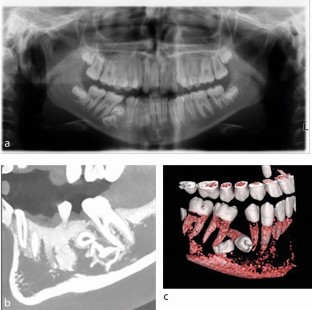

Primary molar teeth that are retained beyond their exfoliation pose a clinical decision-making challenge for dental teams. The retention of these teeth may be due to absence of a permanent successor. As a result, careful planning is required to determine if retention or extraction is necessary. This article aims to discuss the prevalence of retained primary molars, assessment and treatment planning considerations, from both orthodontic and restorative perspectives.

Explains considerations for extraction of primary molars and consequences if retained, such as infraocclusion.

Hua L, Thomas M, Bhatia S, Bowkett A, Merrett S. To extract or not to extract? Management of infraoccluded second primary molars without successors. Br Dent J 2019; 227: 93-98.